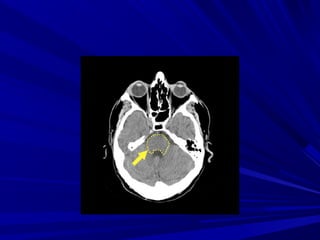

Leâ Vaên H., Nam, 44 tuoåi, Xuaát huyeát

thaân naõo

XUAÁT HUYEÁT THAÂN NAÕOXUAÁT HUYEÁT THAÂN NAÕO